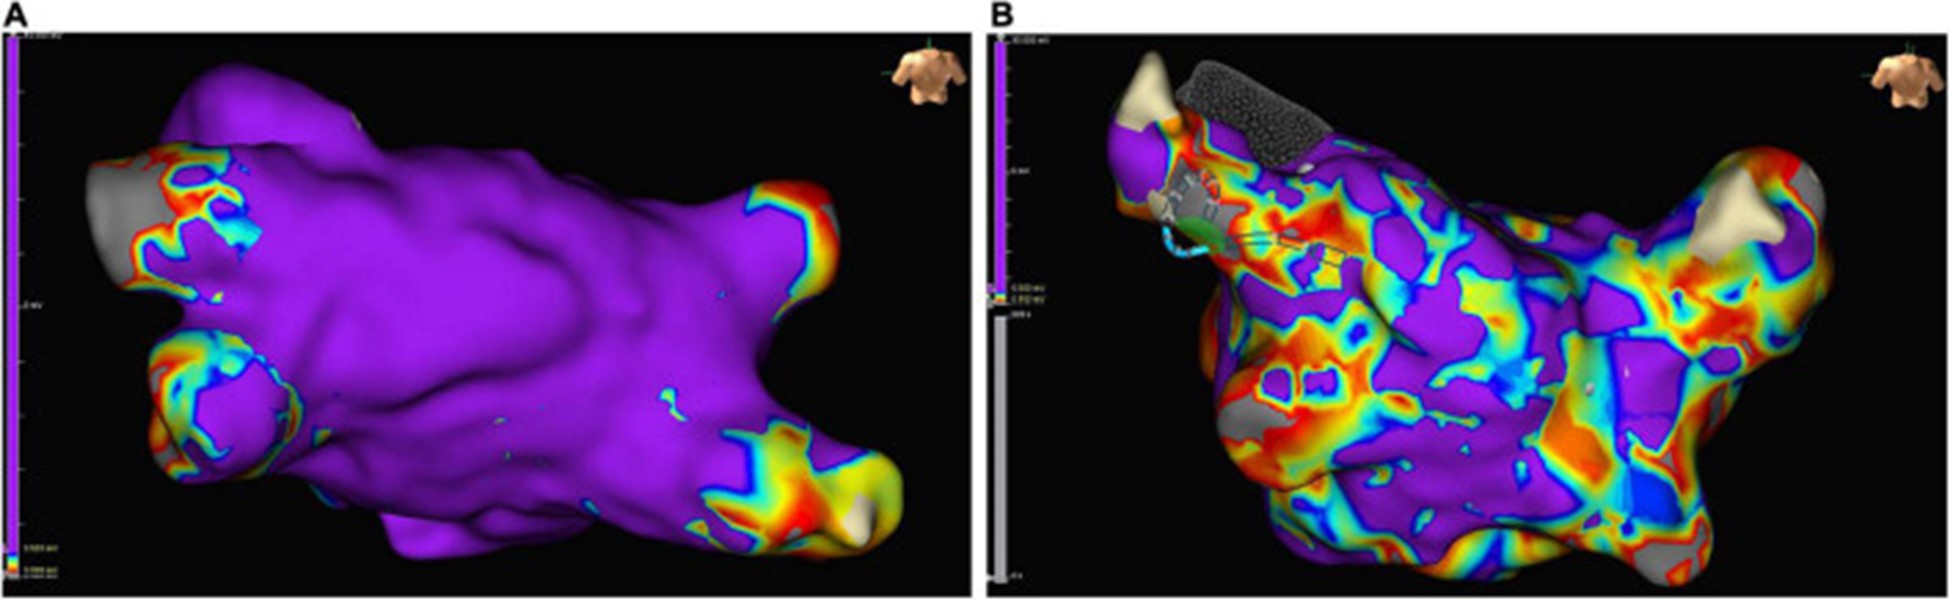

非局灶性 LA 心动过速患者在心内膜标测中出现高比例的低电压区域,为可能的左心房心肌病提供了证据 (图 6)。对纤维化左心房心肌病患者的分析显示,随着纤维化左心房心肌病的严重程度增加,严重的纤维化区域增加,最大 LA 电压降低(101)。

图 6:在接受肺静脉隔离的窦性心律患者的左心房心内膜标测中的低电压区域示例:正常传导的心房心肌呈紫色,低电压区域(定义为电感知幅度≤0.5 mV的区域)是颜色不同。(A)几乎没有低电压区域的左心房示例。(B)低电压区域 > 10% 的严重疾病左心房示例。